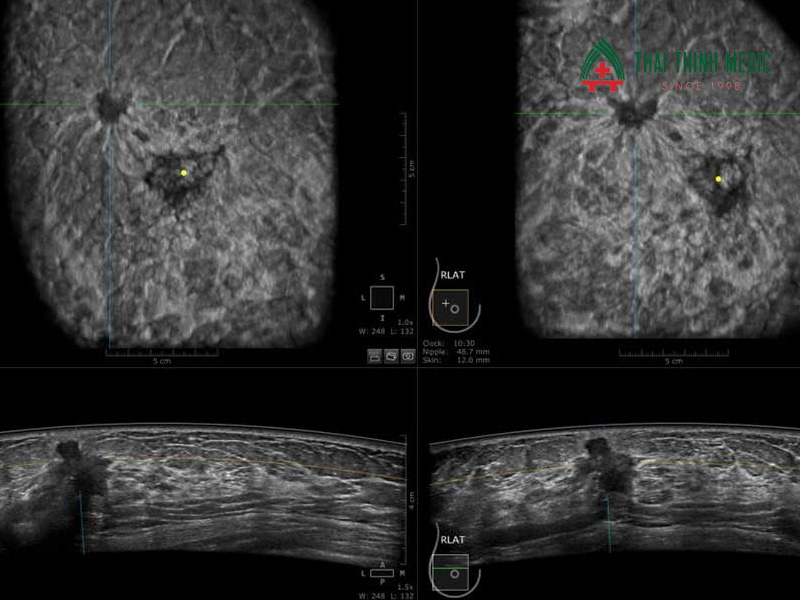

Siêu âm vú là phương pháp chẩn đoán hình ảnh, sử dụng sóng âm tần số cao giúp thu được những hình ảnh bên trong mô tuyến vú. Kỹ thuật siêu âm tuyến vú giúp các bác sĩ quan sát được cấu trúc bên trong của vú, giúp phát hiện các bất thường như u xơ, u nang, viêm tuyến vú hay những dấu hiệu nghi ngờ ung thư vú.

- Trong quá trình siêu âm, bác sĩ sẽ phóng to hình ảnh và ghi lại hình ảnh hoặc đo kích thước khối bất thường nếu được phát hiện.

Siêu âm có thể nhận diện được các khối u có kích thước nhỏ, nang dịch hoặc khối đặc bất thường.

Giúp các bác sĩ có thể quan sát được hình dạng, ranh giới và mật độ mô của khối u – những yếu tố quan trọng để phân biệt u lành hay u ác.